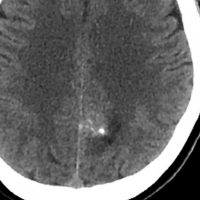

神経節細胞腫は放射線治療抵抗性

Tourette syndrome(音声と行動のチック,不随意運動)で発症した男児です。石灰化もありのう胞も伴う大脳基底核gangliocytoma grade 1で,摘出にはリスクがあると判断して46グレイ23分割の定位放射線治療をしました。しかし治療抵抗性で増大したために,上側頭溝からの経路で腫瘍を摘出(右の画像)しました。それ以来13年が経ちますが再発はありません。グレード1の神経節細胞腫は放射線治療抵抗性のものが多いと考えた方がいいし,より大きな線量を使用しても同じ結果なのでしょう。